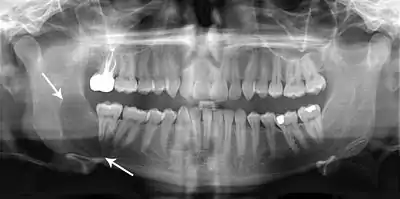

Diagnosis is usually radiological. However, definitive diagnosis is through biopsy. Aspirational biopsy of odontogenic keratocysts contains a greasy fluid which is pale in colour and contains keratotic squames.[12][2] Protein content of cyst fluid below 4g% is diagnostic of odontogenic keratocysts.[2] Smaller and unilocular lesions resembling other types of cysts may require a biopsy to confirm the diagnosis.[9] On a CT scan, the radiodensity of a keratocystic odontogenic tumour is about 30 Hounsfield units, which is about the same as ameloblastomas. However, ameloblastomas show more bone expansion and seldom show high density areas.[13]

Radiographs of odontogenic keratocysts show well-defined radiolucent areas with rounded or scalloped margins which are well demarcated.[12] These areas can be multilocular or unilocular. The growth pattern of the lesion is very characteristic from which a diagnosis can be made as there is growth and spread both forward and backward along the medullary cavity with little expansion. No resorption of teeth or inferior dental canal and minimal displacement of teeth is seen. Due to lack of expansion of the odontogenic keratocyst, the lesion can be very large when radiographically discovered.[9]